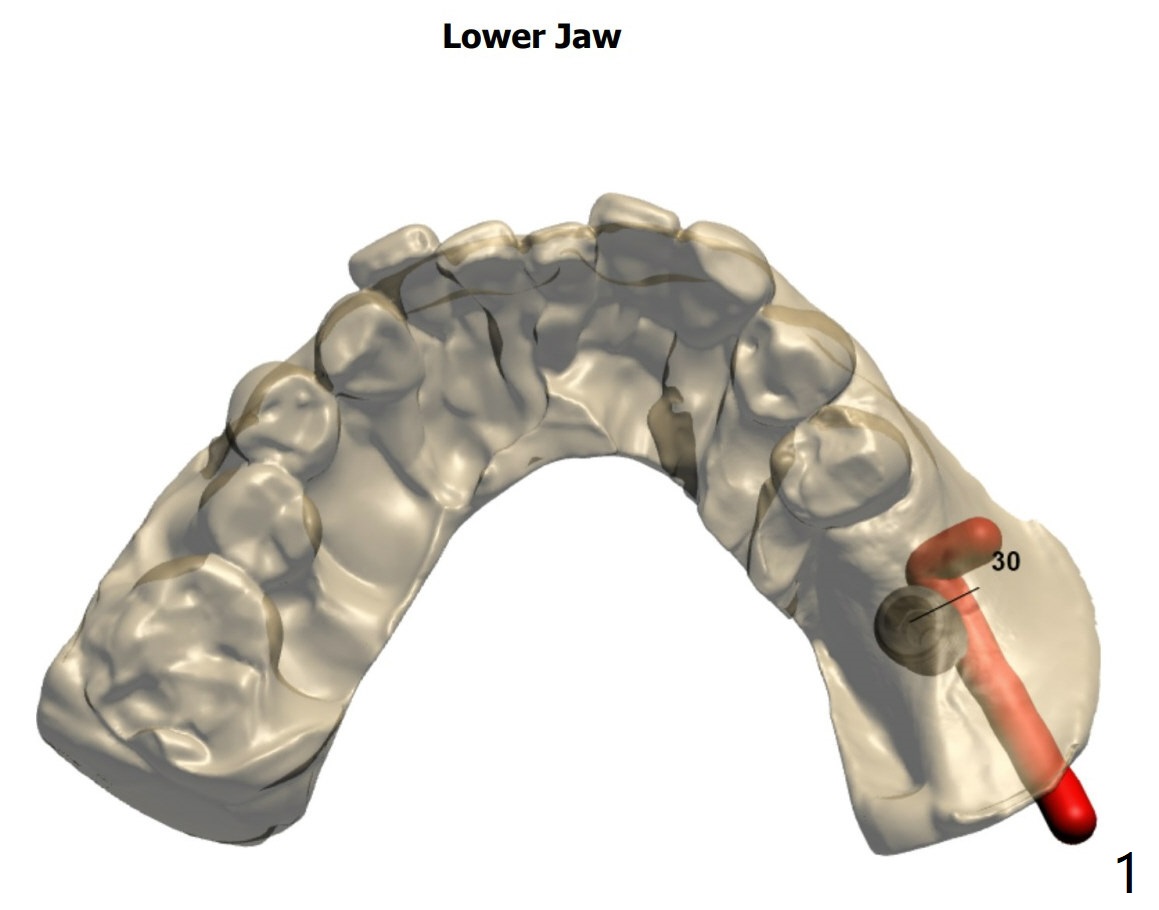

植体

近中牙槽嵴高,植牙后需要profile drill